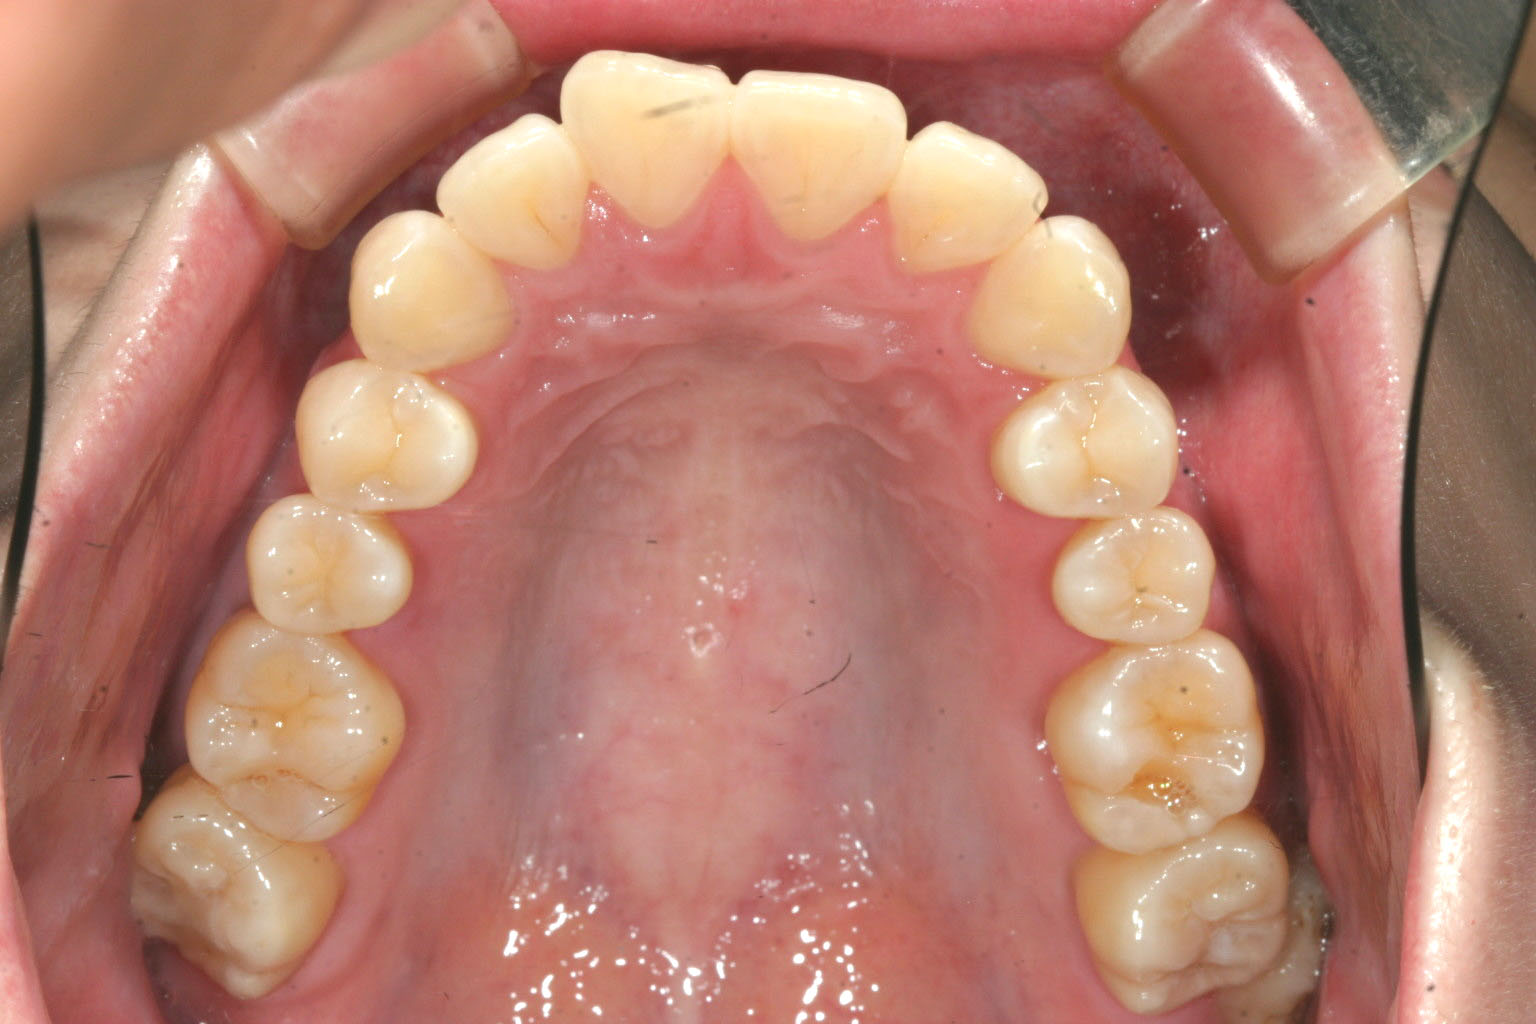

咬合面観はさほどアーチは乱れていません。